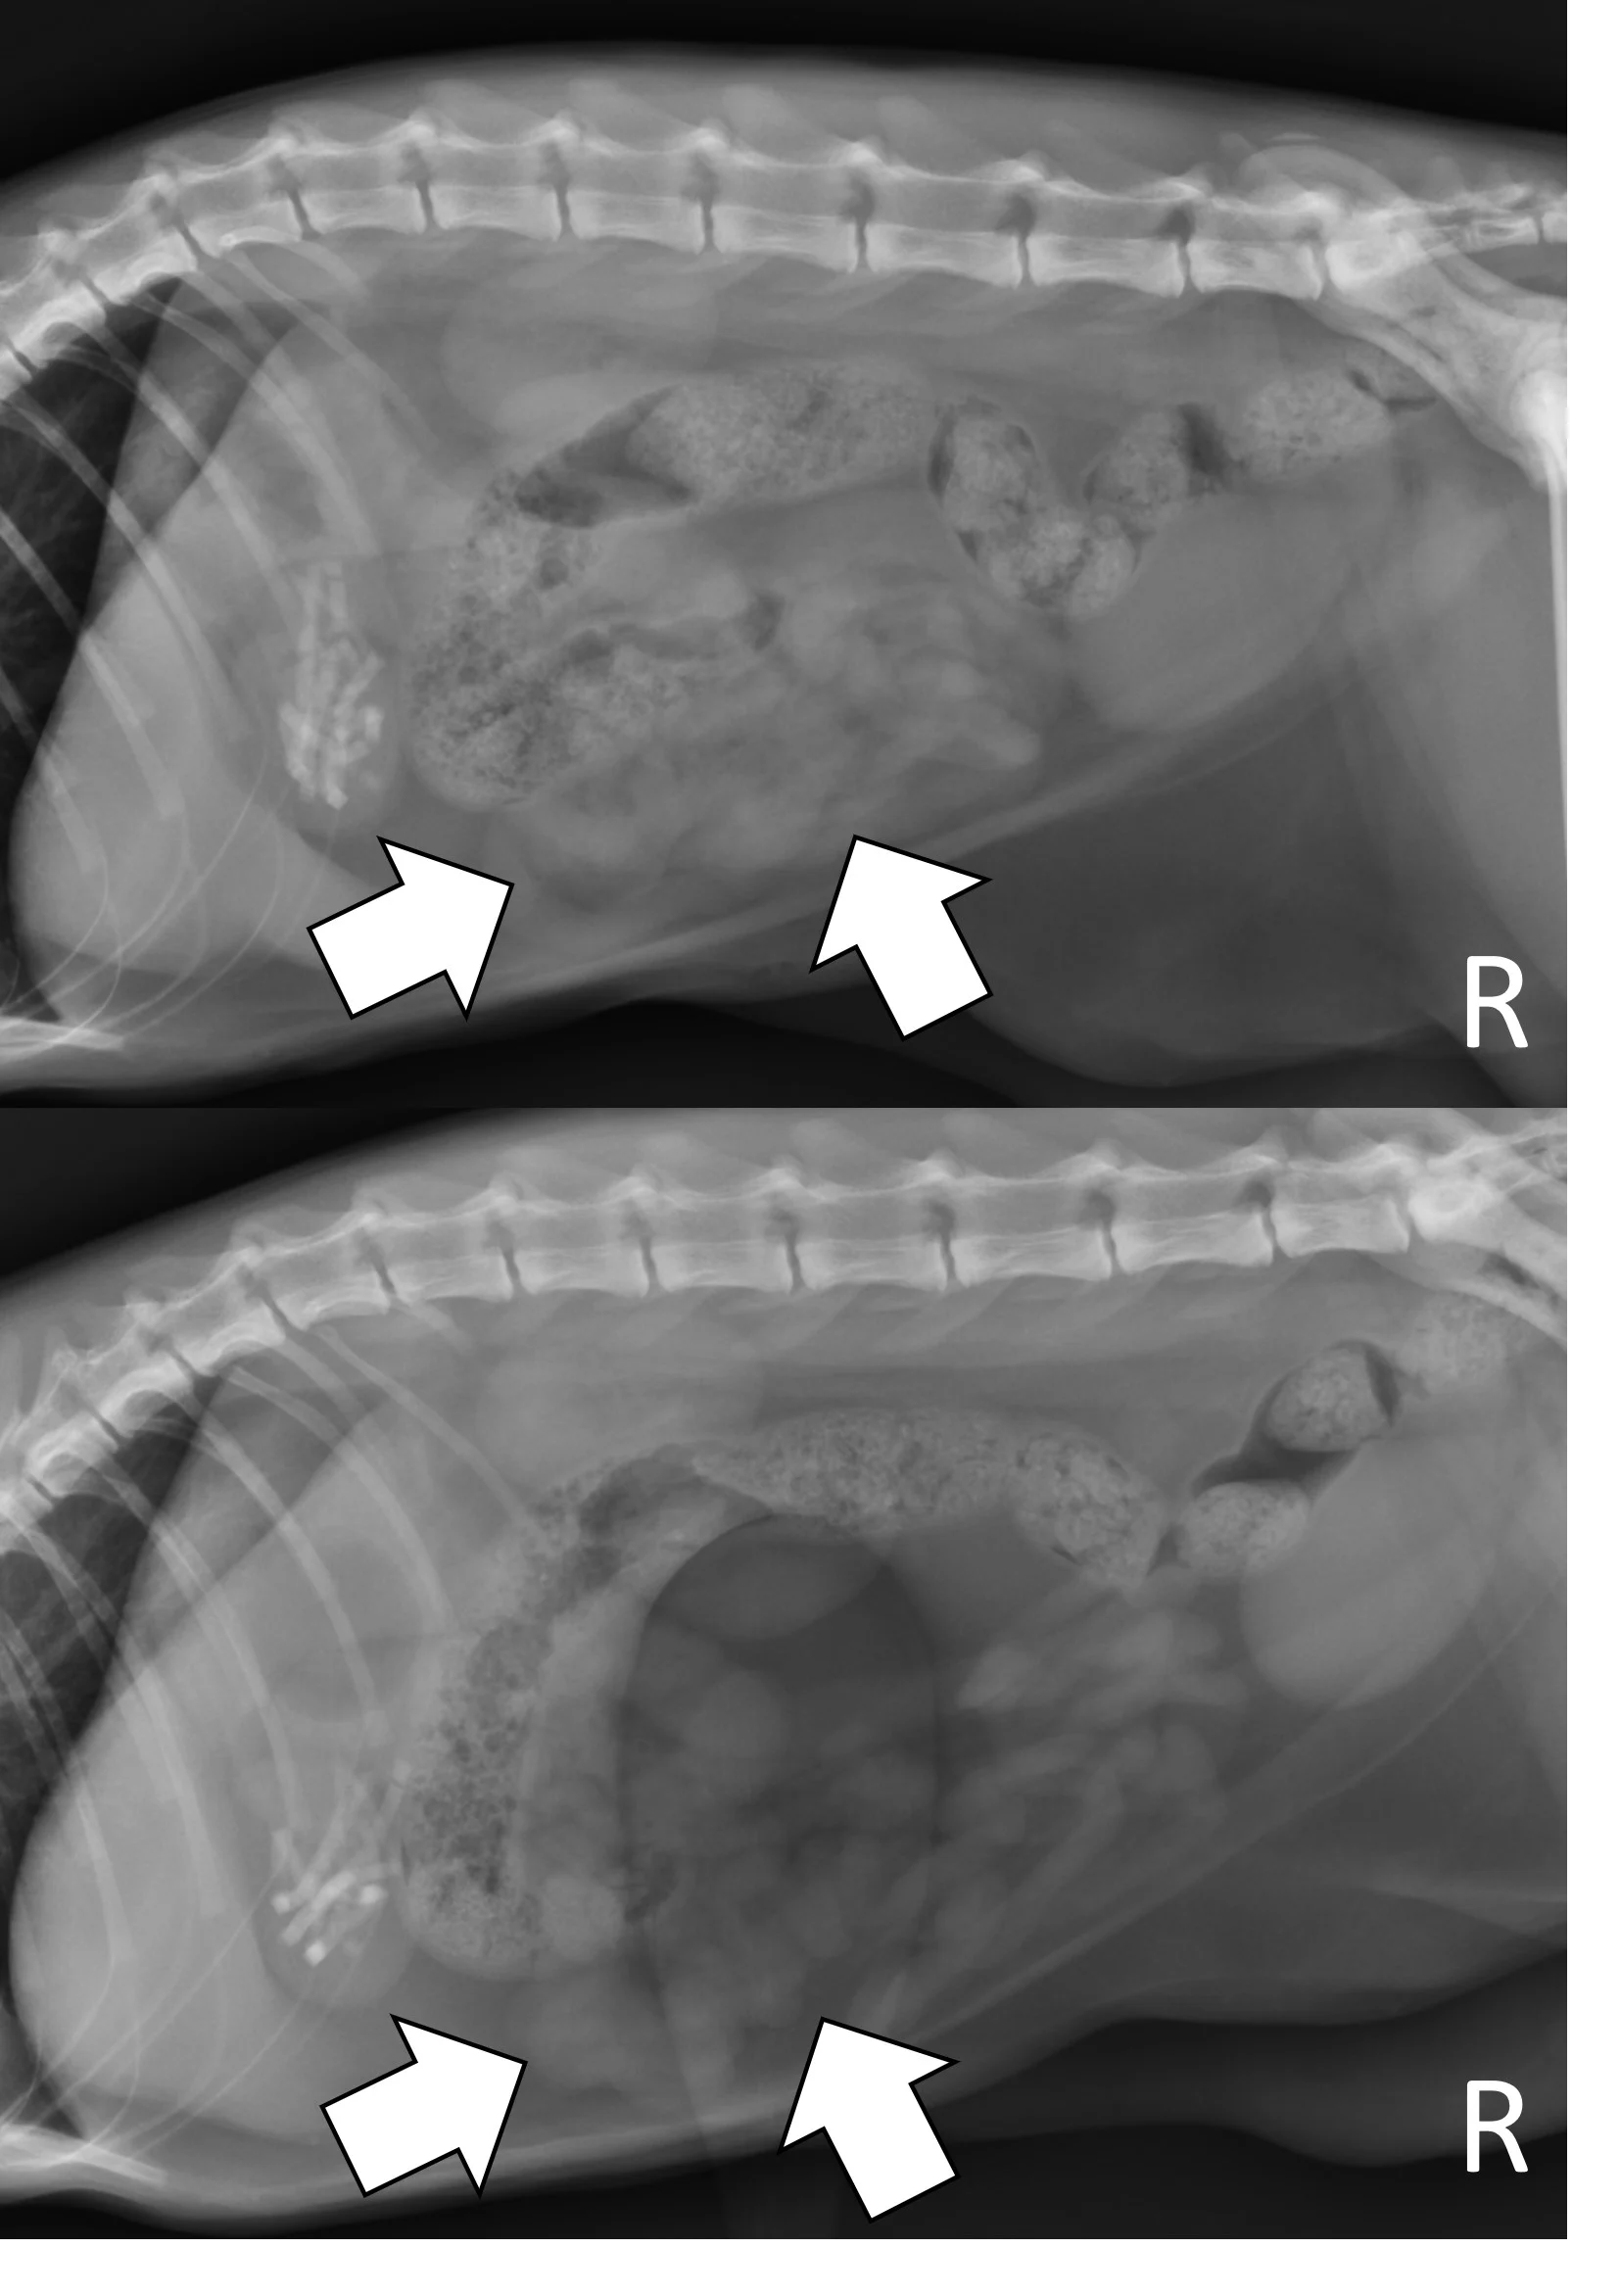

Right lateral and ventrodorsal abdominal radiographs of a male dog (unknown age, breed, and neuter status) with a surgically confirmed acute linear foreign body (cloth) obstruction. Portions of the small bowel are segmentally dilated with bunching and angular or crescent-shaped gas bubbles (arrows).

Right lateral radiographs of a 6-month-old spayed seal point crossbreed cat with a surgically confirmed acute linear foreign body (hair entangled in hair ties) obstruction. The small bowel is bunched in the midabdomen, making the plicated small bowel difficult to see (top, arrows). Normal small bowel displaces after compression with a wooden spoon, but the plicated bowel remains stationary and is easier to see (bottom, arrows).